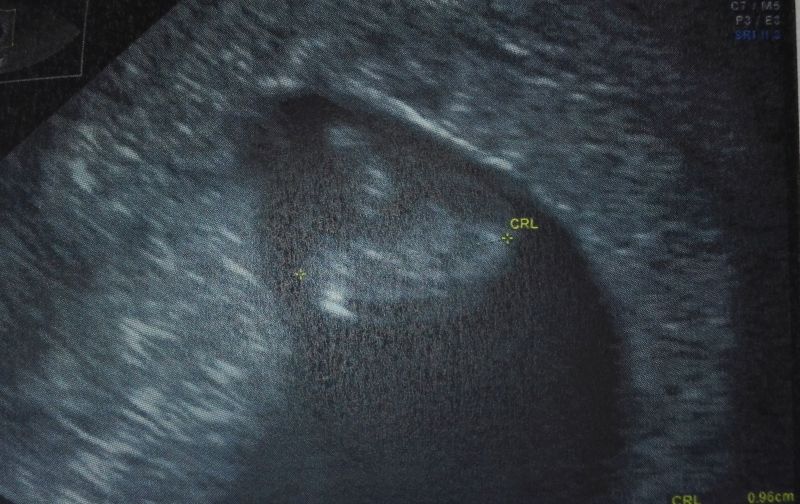

no fajnie by było co nie tak dla odmianyWedług tego kalendarza powinnam mieć już dwie dziewczynki [emoji3] a teraz mi wychodzi chłopak. To moze u mnie na odwrót i zamiast chlopca będzie dziewczynkachciałabym... Zwariuje z czterema facetami pod jednym dachem [emoji33]